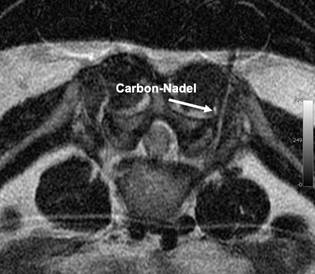

Periradikuläre Therapie unterm MRT

Die PRT unterm MRT ist eine ergänzende Methode zur etablierten CT-gestützten PRT. Der Vorteil ist , dass keine Strahlung notwendig ist. Da sich in der Beckenregion die Geschlechtsorgane befinden, ist dies durchaus sinnvoll. Demgegeüber stehen höhere Kosten und ein höherer Zeitaufwand. Es können zudem keine herkömmlichen metallischen Instrumente eingesetzt werden, da sie das Magnetfeld beeinflussen und im Bild Störungen, so genannte Artefakte, hervorrufen würden. Neue Carbon-Nadeln stören das Bild nicht und eignen sich bestems für den Einsatz im MRT. Die mechanischen Eigenschaften der Nadel sind mit herkömmlichen Instrumenten aus Edelstahl durchaus zu vergleichen.